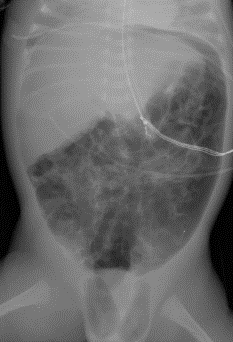

1

small bowel obstruction

dilated loops of small bowel, paucity of bowel gas distally

normal for comparison